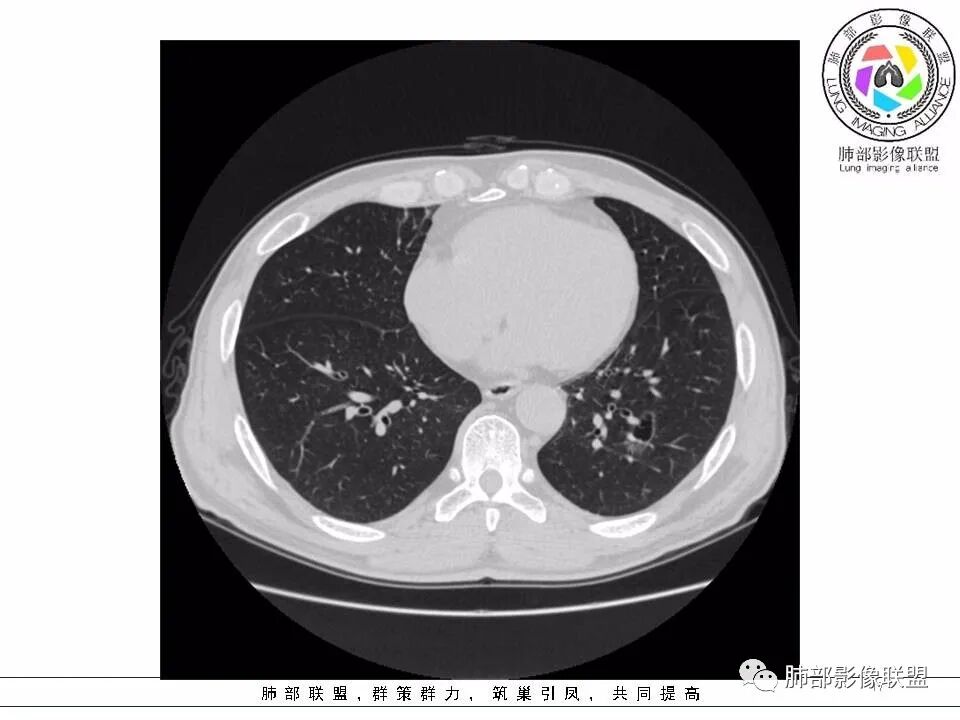

【每日晨读】黄色预警--警惕囊腔型的病变

左肺下叶囊腔,壁厚薄不均,可见磨玻璃成分!考虑恶性可能,腺癌?

左下肺囊性病变,边界不规则,有磨玻璃,内分隔,壁厚薄不均,内有壁结节,考虑囊腔样腺癌。

男性,发热,肿瘤标志物不高,影像:左下肺类圆形囊腔,内有丝丝缕缕,周边有渗出,右肺少许条索,第一印象:囊腔型腺癌

老年男性,左肺下叶囊腔,与临近支气管关系紧密,壁厚薄不均,周围可见实性成分,腔内密度不均匀,可见索条及结节,考虑囊腔型肺癌

男性患者,左肺下叶囊性病变,壁厚薄不均,部分壁较厚,周围可见磨玻璃影,考虑周围型肺癌,腺癌可能。

左下肺囊性病变,边界不规则,周围见磨玻璃影,内分隔,壁厚薄不均,考虑囊腔样腺癌可能性大,鉴别肺大泡合并感染,首次发现建议至少复查一次看看。

中年男性,发热伴咳少量白痰,左下肺可见一囊性空腔,壁厚薄不均,局部周围GGO,边界较清,内见分隔及结节,常规考虑囊腔性腺癌

间断发热半月余。半月前无明显诱因出现发热,体温波动于38℃,畏寒,轻咳,少量白痰,时有活动后胸闷气喘。无胸痛、心慌、乏力、盗汗、消瘦、咯血。于当地诊所予以头孢静脉输注一周,体温正常3天后再次出现体温升高。波动于37.2℃。实验室检查没有太多的问题。左肺下叶囊腔病变,壁比较薄,部分环壁局限性的增厚,边界毛糙,略显模糊,并见与支气管相连,未见明显的壁结节,而囊壁内见丝丝缕缕的索状影。考虑良性病变,毛霉菌感染或隐形性感染,鉴别寄生虫肺部感染。

2.左肺下叶外基底段囊腔样病灶,轮廓柔和,壁厚薄不均,见壁结节。内见分隔或脊状突起。腔内见血管穿行。

这是有“故事”的囊!

3.囊壁外环以磨玻璃影,边界较清楚。

1.囊腔壁厚薄不均,壁结节,内有分隔,其内有血管穿行,指向新生物。

2.临近有边界清楚磨玻璃影,指向腺癌。